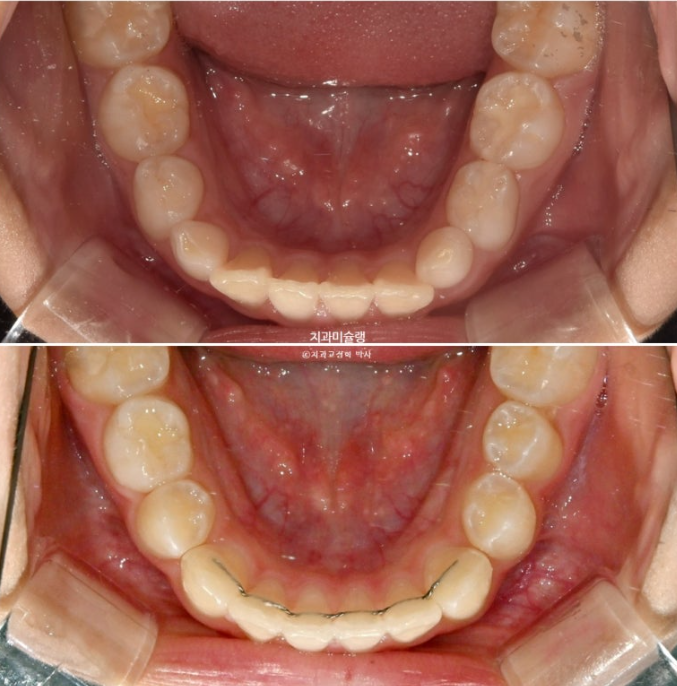

이제 전 후 비교 볼게요

23.10~25.11

나중에 성인이 되어 2차교정을 안해도 될 정도의 완성도 입니다.